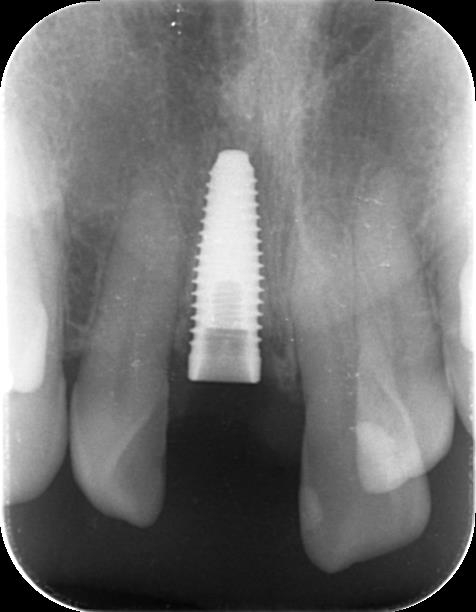

術後のデンタル写真